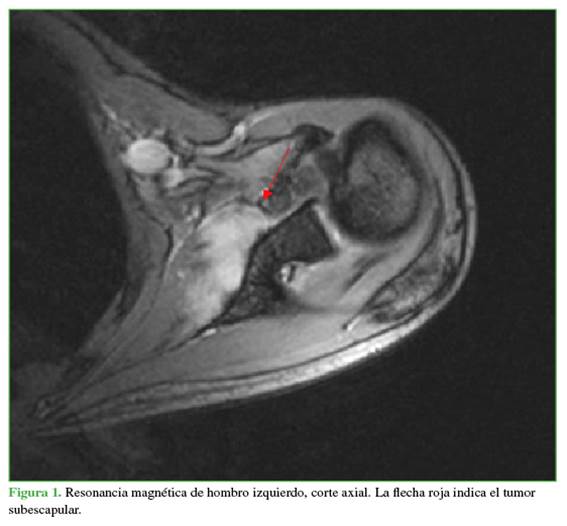

Mujer de 28 años, con antecedentes de escoliosis idiopática del adulto y con un trabajo activo que implicaba la carga de material. Fue derivada a consultas externas de traumatología por omalgia izquierda postraumática de ocho meses de evolución y limitación para la rotación externa, contractura y dolor a nivel del trapecio, sin mejoría tras la rehabilitación. En el examen físico, se detectó hipotrofia relativa de la musculatura escapulohumeral izquierda en comparación con la contralateral. No se palparon masas ni se observaron signos inflamatorios. La movilidad activa y la pasiva estaban conservadas, a excepción de una rotación externa de 0º para el hombro izquierdo y de 75º para el hombro derecho. Asimismo, se constató una discinesia escapulotorácica compatible con una escápula alada izquierda, por lo que se le solicitaron diferentes estudios complementarios. Con la tomografía computarizada, se descartó una enfermedad ósea. En la electromiografía, se detectó una lesión del nervio torácico largo, con características crónicas y de intensidad moderada, lo que impedía la movilidad de la escápula. Además, la resonancia magnética reveló una lesión en el músculo subescapular de unos 5 cm, con bordes pobremente diferenciados, discreta heterogeneidad y ligera hiperintensidad de la señal potenciada en T2, compatible con un proceso fibromatoso (Figuras 1 y 2).